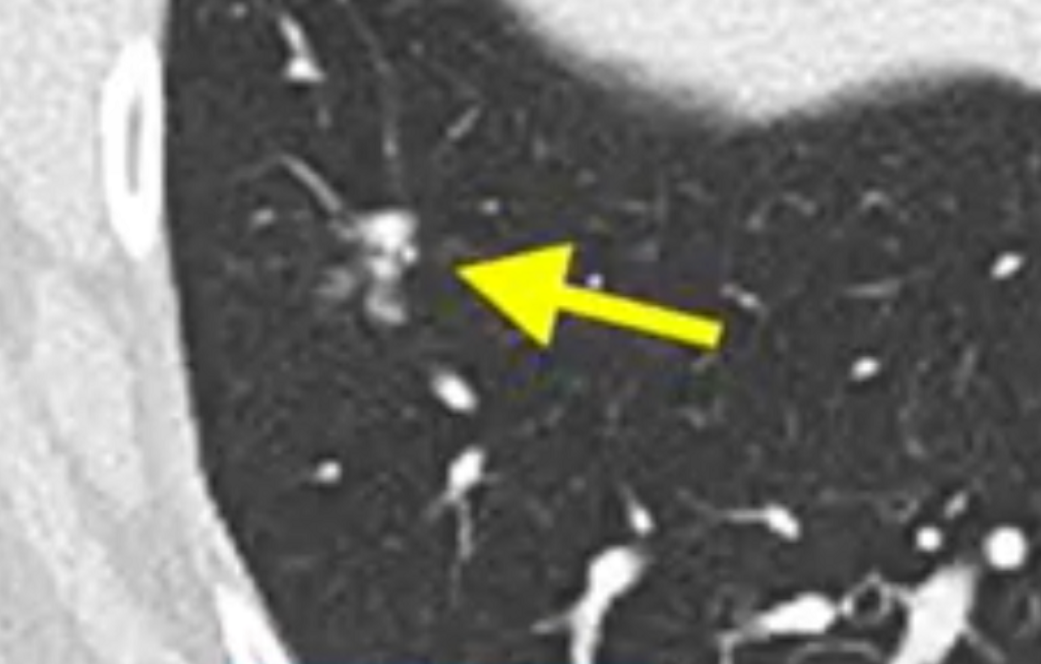

40天后,Ryan女士第一次复查惊讶的发现,肺上剩余的7个转移病灶已经全部消退,其中三个完全消失,医生们惊呼这是新型免疫疗法带来的又一例奇迹,Ryan女士在4年后仍然没有疾病进展,并且和Bachini女士成为好朋友。